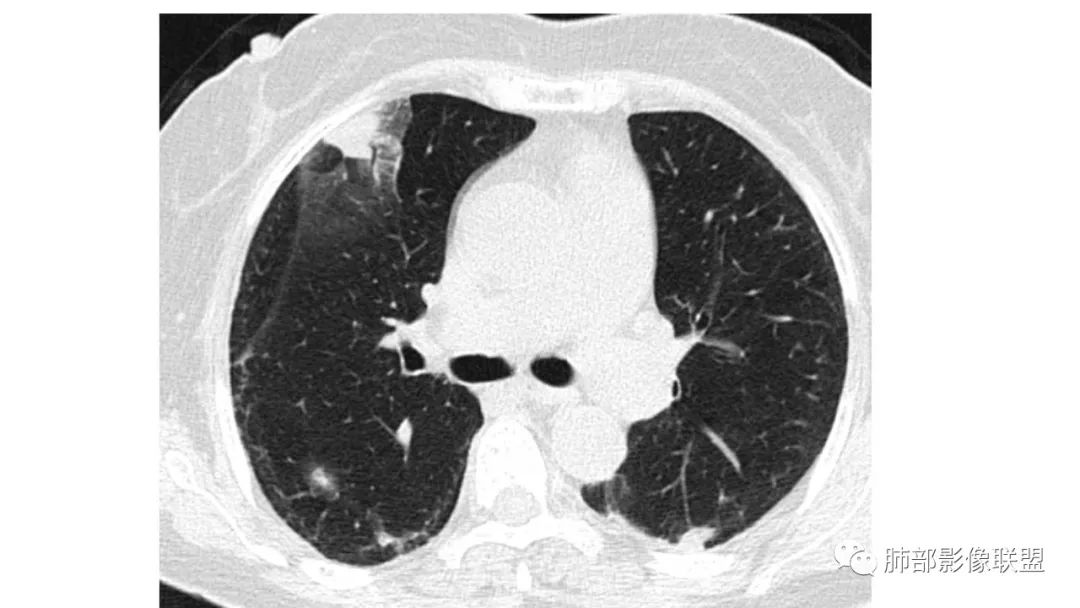

二、肺炎型

2、病灶常有一个主病灶,常位于下肺。后沿气道播散为多发病灶。

3、重力作用,叠瓦征。近叶间裂因重力效应,呈膨隆改变。

4、增强后不均匀强化,存在低强化区呈弱强化或无强化,因此可见“血管造影征。”血管毛糙与肺炎有统计学差异。

5、支气管粗细不均,呈“枯树枝征”,但与肺炎这一点鉴别不具有统计学差异。可发生支气管扩张

6、空腔形成,部分蜂窝状改变。

8、斑片常伴有结节,边缘清楚GGO或欠清楚。

9.粘液腺癌的变化规律:结节缓慢发展而来,向周围播散形成斑片后可快速进展,有时支气管镜后或粘液排出后局部可形成好转的假象。病灶可沿肺泡和支气管播散。

三、本例是一个误诊多年的病例,给我们很多启示:

2.粘液腺癌易伪装成肺炎的形态,尤其是当患者本身具有免疫色彩的时候,易误诊为间质性肺炎,或肺部感染。若治疗无效,取得病理很重要。

4.回到本例,左下肺病变两次好转,均未经过肿瘤治疗,第一次是支气管镜后,第二次是当其他病变都在进展的情况下,左下肺病变范围反而缩小趋于浅淡。